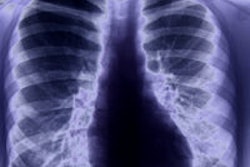

Significant numbers of departments are claiming radiographer-led CT, MRI, and ultrasound diagnostic studies as well as interventional procedures, according to the Scope of Radiographic Practice Survey 2012.